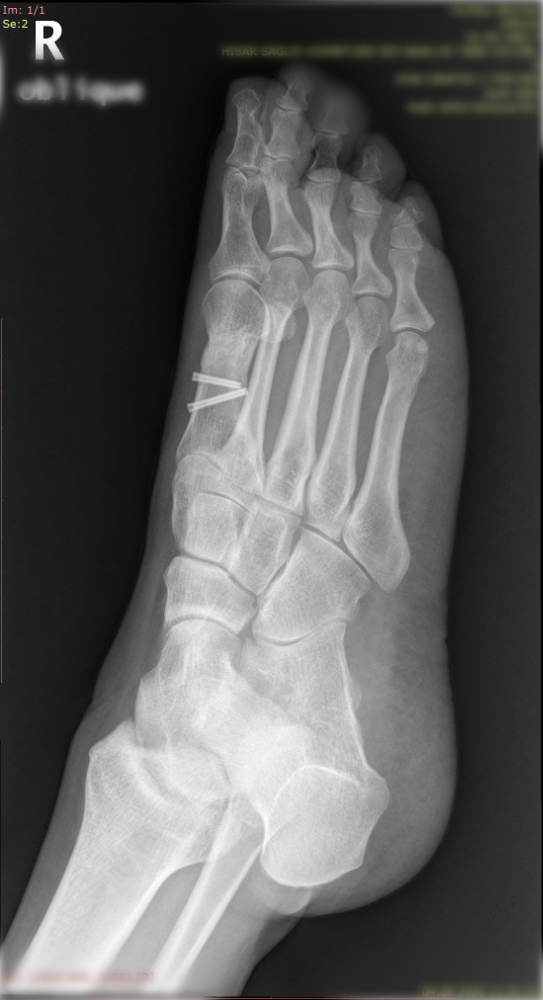

Halluk valgus ayak baş parmağının zaman içerisinde değişik nedenlerle eğilmesi ile ayak yan tarafında çıkıntının da eşlik ettiği bir rahatsızlıktır. Sıklıkla bayanlarda görülmesine rağmen erkeklerde ve çocukluk yaşlarında da karşılaşılmaktadır. Ayağın yan tarafında olan çıktı ve baş parmağın diğer parmakları itmesi ile ayakta şekil bozukluğu ve ağrı oluşur. Bu şekil bozukluğu kişinin ayakkabı giymesinde sıkıntılara neden olabilir.

Tedavisinde ayağın yük veriri pozisyonda çekilen grafileri üzerinde yapılan ölçümlerden sonra hastanın yaşı ve aktivite seviyesine göre kişiye özel planlanmaktadır. Erken dönemlerde ayakkabı modifikasyonu, parmak arası makarası ve gece ateli kullanılmaktadır. Cerrahi gerekliliğe hastanın deformitesinin büyüklüğüne ve hastanın taleplerine göre karar verilmektedir.

Aşağıdaki grafiyi öncesi sonrası şeklinde görmek için farenizi sağ sola hareket ettiriniz.

Yukarıdaki grafileri daha net ve büyük görmek için üzerine tıklayabilir. Sağ üst köşedeki + - tuşları ile daha da büyütebilirsiniz.